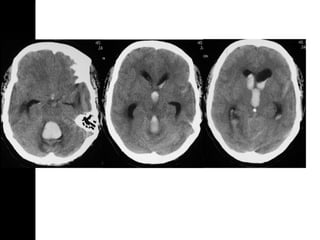

Intraparenchymal hematomaIntraparenchymal hematoma Focalcollections of blood that most commonly arise from shear-strain injury to intraparenchymal vessels. Usually located in the frontotemporal white matter or basal ganglia Hematoma within normal brain DDx: DAI, hemorrhagic contusion

• 26.